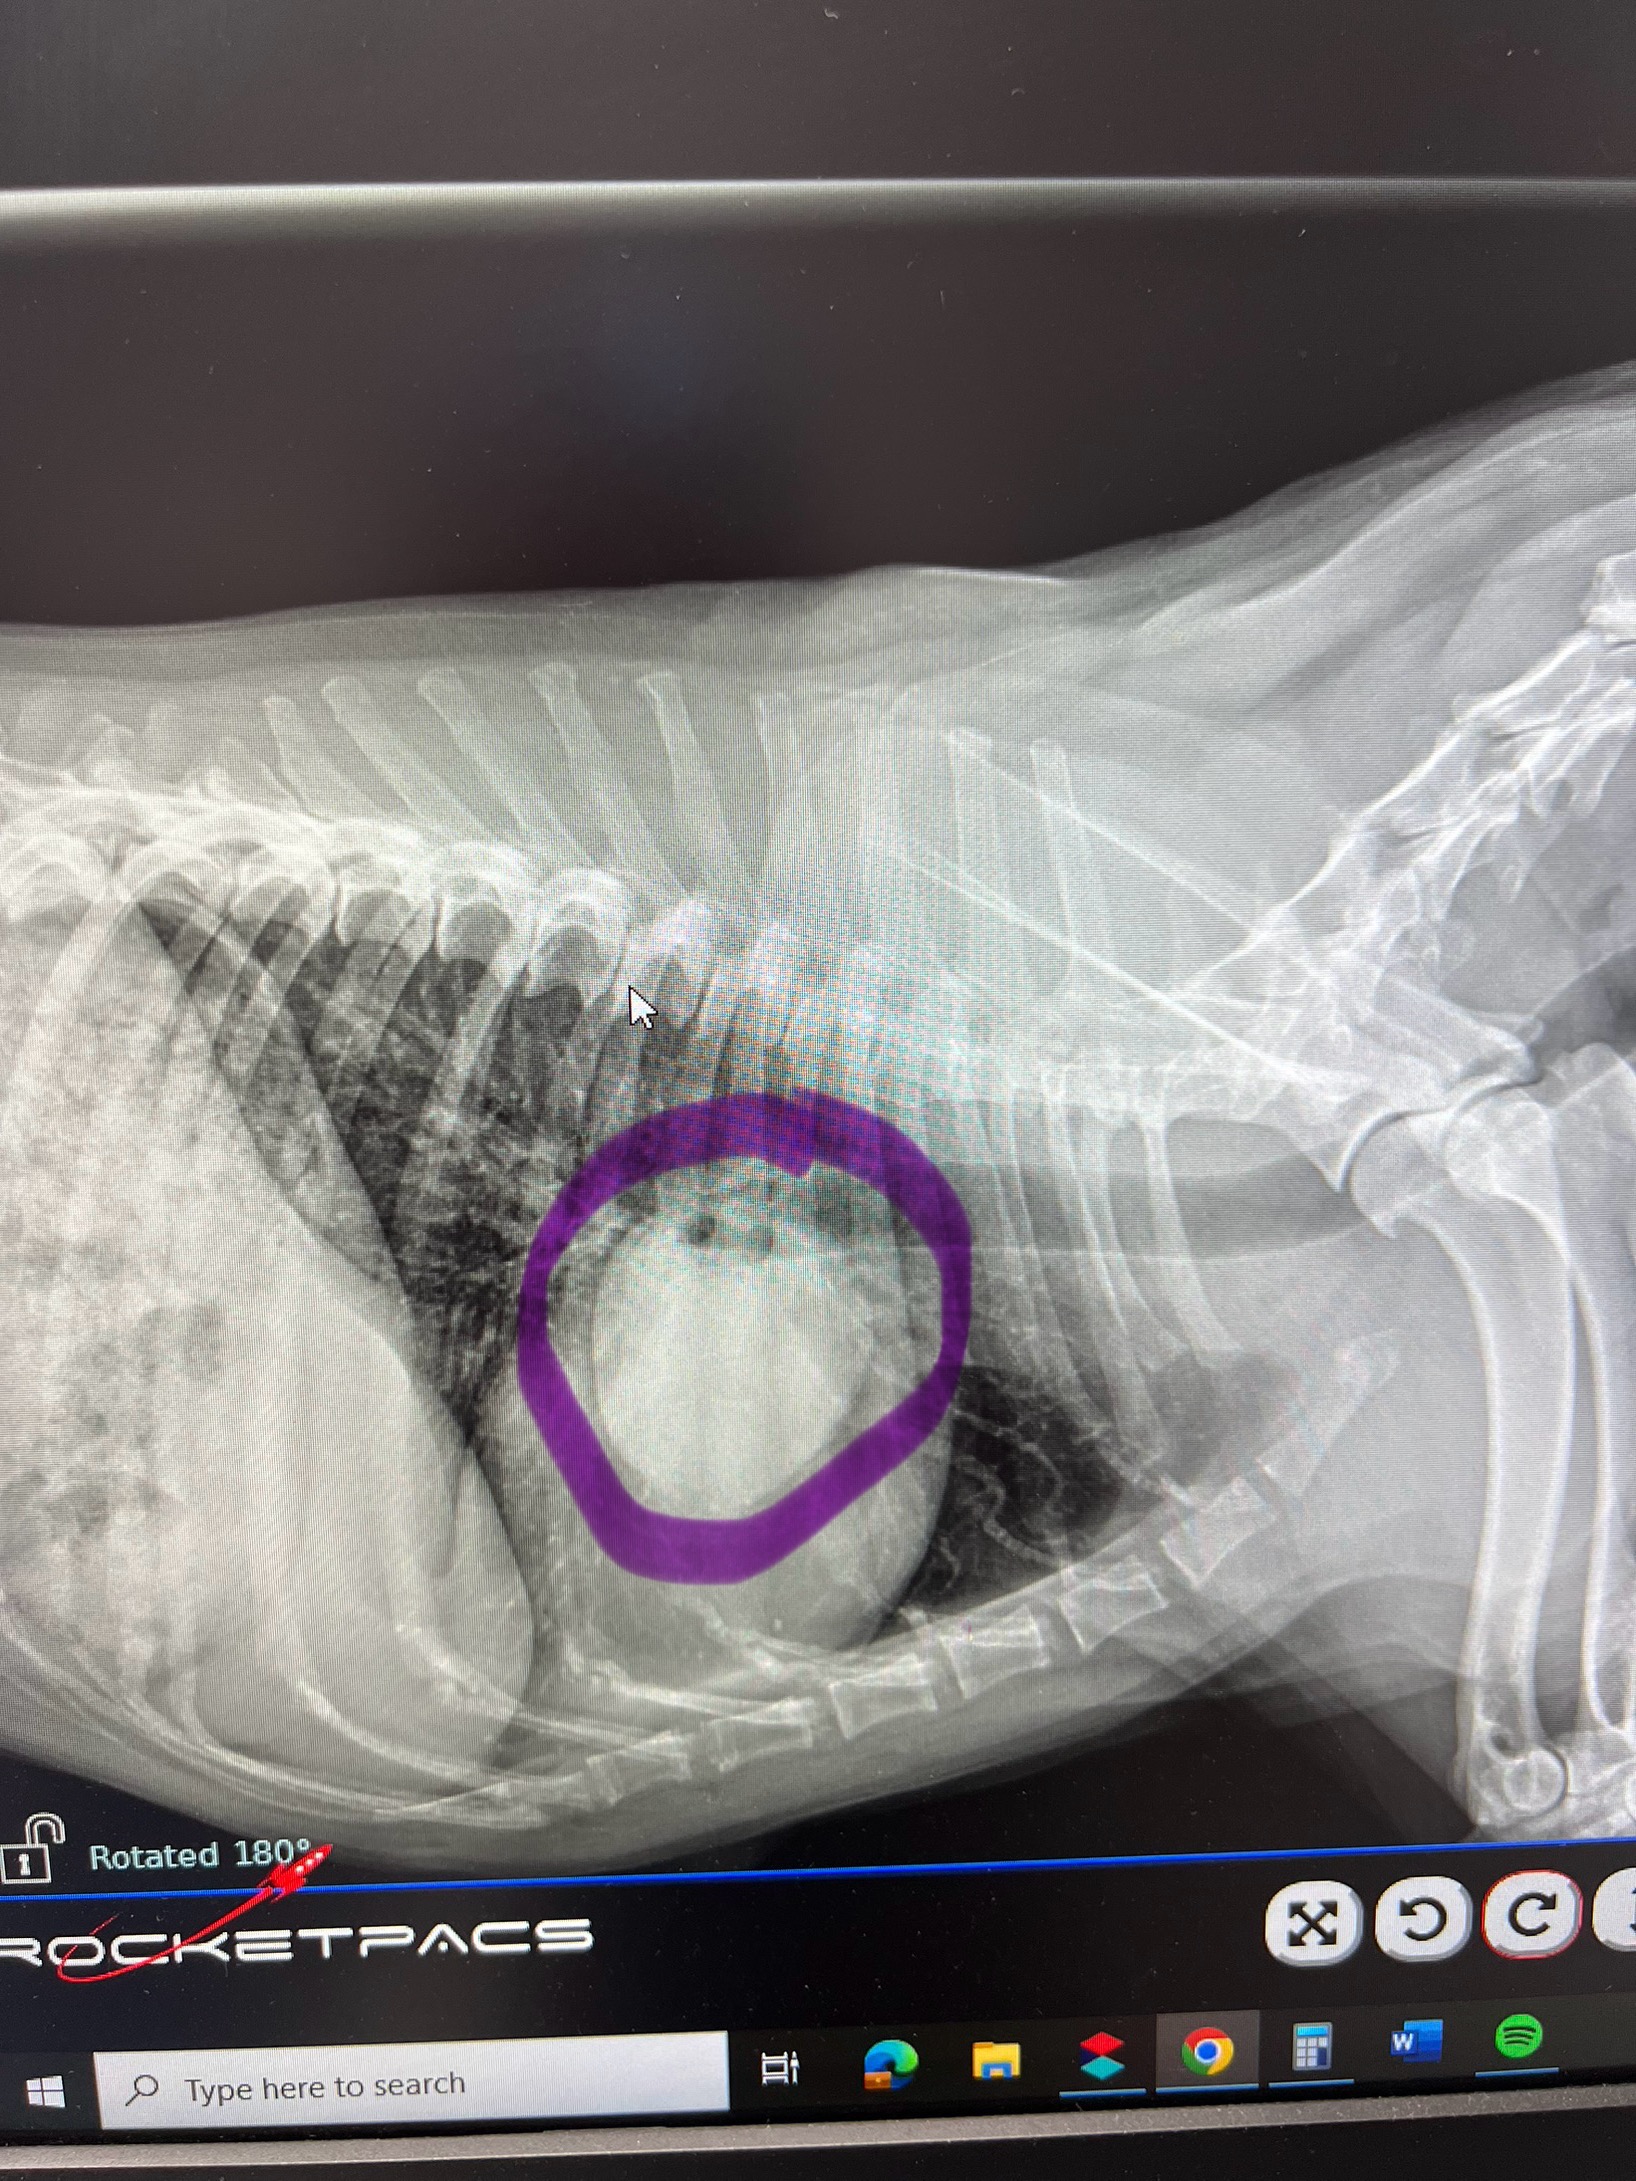

Hello! My name is Amanda Korytko and if you know me, you know that my dog Gator is my pride and joy! Gator was taken in for a cough to the vet and unfortunately, that's when they found a cancerous tumor on his right lung. As you know, chemo, radiation, surgery, CT scans, medications, and doctor visits are very costly. With me being out on my own medical leave due to a surgery, times are a bit tough. Gator still has a lot of love and joy to give! Anything helps and will all be put towards his care. Gator and I both thank you all. ❤️